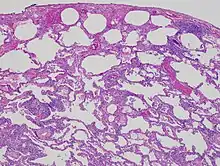

Low magnification view of the histology of chronic hypersensitivity pneumonitis. The interstitium is expanded by a chronic inflammatory infiltrate. Two multinucleated giant cells can be seen within the interstitium at left, and a plug of organizing pneumonia at bottom left.

Lung biopsies can be diagnostic in cases of chronic hypersensitivity pneumonitis, or may help to suggest the diagnosis and trigger or intensify the search for an allergen. The main feature of chronic hypersensitivity pneumonitis on lung biopsies is expansion of the interstitium by lymphocytes accompanied by an occasional multinucleated giant cell or loose granuloma.[7][22]

When fibrosis develops in chronic hypersensitivity pneumonitis, the differential diagnosis in lung biopsies includes the idiopathic interstitial pneumonias.[23] This group of diseases includes usual interstitial pneumonia, non-specific interstitial pneumonia and cryptogenic organizing pneumonia, among others.[7][22]

The prognosis of some idiopathic interstitial pneumonias, e.g. idiopathic usual interstitial pneumonia (i.e. idiopathic pulmonary fibrosis), are very poor and the treatments of little help. This contrasts the prognosis (and treatment) for hypersensitivity pneumonitis, which is generally fairly good if the allergen is identified and exposures to it significantly reduced or eliminated. Thus, a lung biopsy, in some cases, may make a decisive difference.